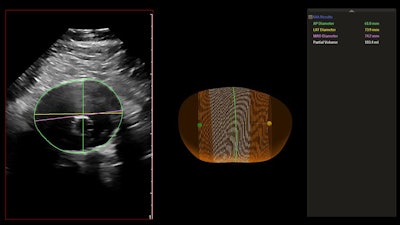

Philips Healthcare parent Royal Philips has introduced 3D ultrasound-based technology to monitor abdominal aortic aneurysms (AAAs).

The company's AAA model is designed to assist clinicians by providing key measurements, including the partial volume and centerline of aneurysms.